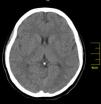

Case reportA 27-year-old primigravida woman presented in the emergency room seven days after an uncomplicated spontaneous vaginal delivery. She complained of recurrent temporary speech disturbance and visual impairment twice within six hours. The pregnancy was uneventful and her medical history was insignificant. On physical examination, blood pressure was 110/65 mmHg with a regular heart rate of 105 bpm. Bilateral grade 1–2 pitting pedal edema was present. Carotid auscultation and fundoscopic evaluation were normal. Chest auscultation showed bibasal crackling rales less than one-half way up the posterior lung fields and an apical III/VI systolic murmur with S3 gallop. The electrocardiogram showed normal sinus rhythm. The chest X-ray on admission showed cardiomegaly and pulmonary edema with bilateral pleural effusion. Urgent neurologic investigation with computed brain tomography revealed no evidence of ischemia (Figure 1). The patient was diagnosed with transient ischemic attack. Laboratory tests, including coagulation studies with platelets, D-dimers, prothrombin time and activated partial thromboplastin time, were within the normal range except for BNP, which was elevated (1300 pg/ml; normal <100 pg/ml) and C-reactive protein (0.30 mg/dl; normal <0.5). The thyroid hormone profile was normal. Transthoracic echocardiography (TTE) showed global left ventricular hypokinesia, left ventricular end-diastolic dimension of 65 mm with an ejection fraction of 22% (by Simpson's method) and moderate mitral regurgitation. A large mobile mural thrombus was observed in the left ventricular apex (Figure 2A and B). Screening for thrombophilia including antithrombin III, protein C and S, plasminogen, fibrinogen and homocysteine levels was normal and antiphospholipid antibodies, β2-glycoprotein I and anticardiolipin antibodies IgG and IgM were negative. Factor V Leiden, prothrombin 20210A polymorphism and MTHFR mutations were not found. The patient was immediately started on intravenous anticoagulation with low molecular weight heparin as well as angiotensin-converting enzyme inhibitors, diuretics and digoxin. A beta blocker (carvedilol) was added after signs and symptoms of congestive heart failure improved. By one month of follow up she had responded well to medical therapy and was asymptomatic; repeat TTE showed no evidence of thrombi in the left ventricle and ejection fraction had improved to 38%.